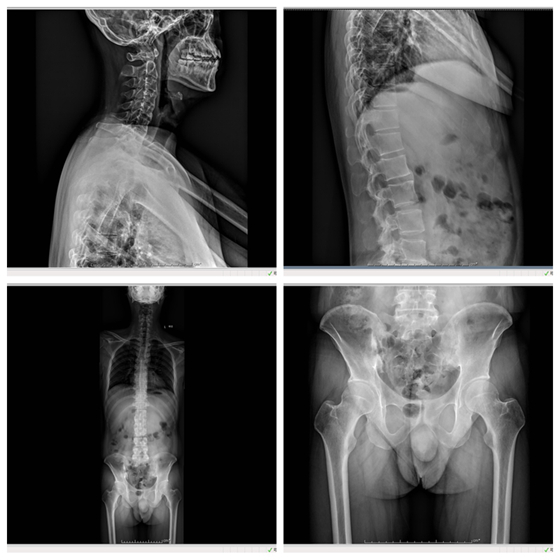

32岁的向先生,最近半年发现脖子不能左右转动,腰也不能弯,体重减轻了近10公斤。向先生说,自己30岁时就开始腰痛,一开始以为是“腰椎间盘突出”,自己吃药、贴膏药也时好时坏,后面经推荐吃了段时间中药,效果也不明显,最近这段时间脖子和弯腰也十分吃力。在家人的陪伴下他来到了湘雅常德医院风湿免疫科。经过仔细的询问病史及检查,确诊为强直性脊柱炎。风湿免疫科主任游运辉亲自为其制定了治疗方案,在经过一周左右的治疗后,向先生的腰痛、脖子疼等症状明显减轻,复查的炎症指标也下降了,本来不能活动的脖子和腰,也能慢慢地转动了,治疗效果很好。

游运辉教授提醒,强直性脊柱炎是一种慢性炎症性疾病,主要侵犯骶髂关节、脊柱骨突、脊柱旁软组织及外周关节,严重者可能发生脊柱畸形和强直,并会伴发关节外表现,25%患者发生眼色素膜炎,反复发作可致视力障碍。多数患者随病情进展由腰椎向胸、颈部脊椎发展,出现相应部位疼痛、活动受限或脊柱畸形。如果能得到及时诊断及合理治疗,可以使症状得到控制并改善预后,防止脊柱或关节变形,提高患者的生活质量。 编辑:胡泽涛 责编:李晓